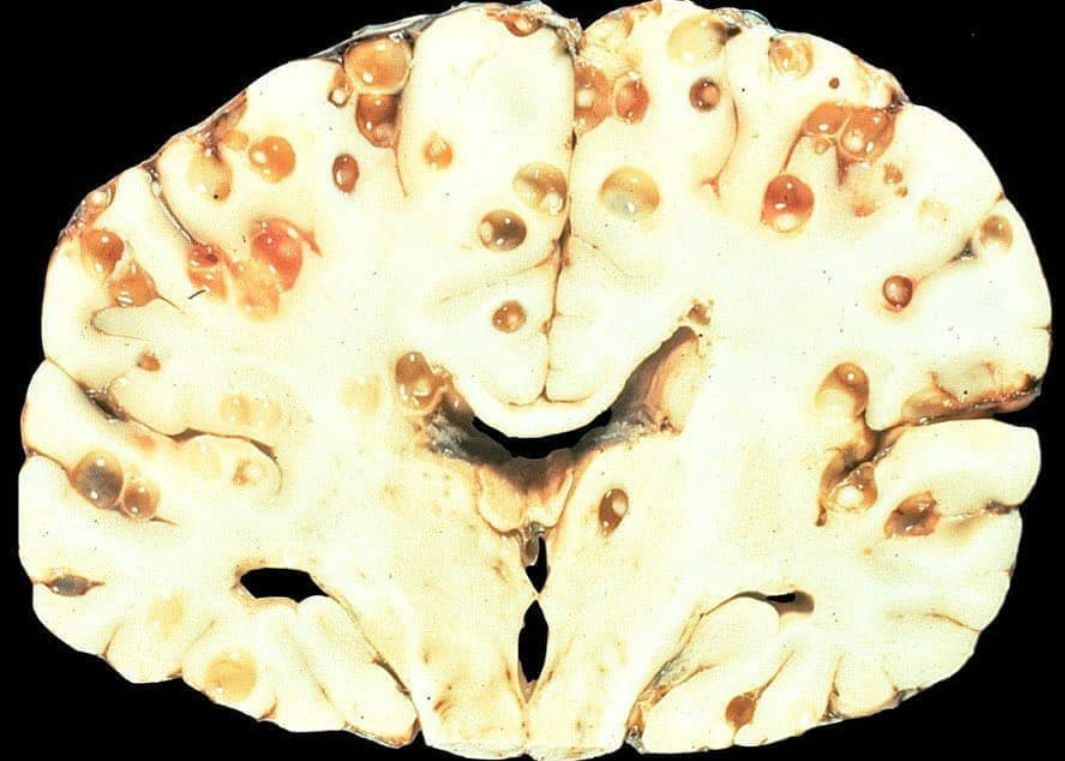

Neurocysticercosis is a specific form of the infectious parasitic disease cysticercosis that is caused by the infection with Taenia solium, a tapeworm found in pigs. Neurocysticercosis occurs when cysts formed by the infection take hold within the brain, causing neurologic syndromes such as epileptic seizures. Common symptoms of neurocysticercosis include seizures, headaches, blindness, meningitis and dementia.